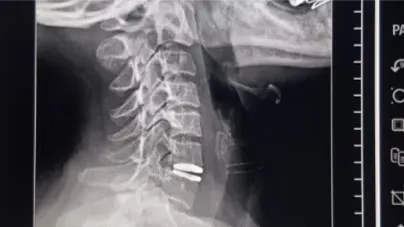

Por primera vez en Villa Mercedes, se realizó una cirugía de reemplazo de disco cervical con prótesis móvil en el sistema público de salud. El procedimiento se concretó el lunes en los nuevos quirófanos del Policlínico Regional ‘Juan Domingo Perón’ y marcó un avance histórico para la medicina local. La paciente, una mujer de 48 años oriunda de Fraga, recibió el alta médica a las 24 horas, con evolución favorable y movilidad preservada.

Gracias a la colocación de una prótesis discal móvil, se logró evitar procedimientos más invasivos y preservar la movilidad de la columna cervical. La cirugía se llevó a cabo en los quirófanos recientemente inaugurados, como parte de la renovación edilicia del Policlínico Regional, que ahora cuenta con tecnología de última generación.

La paciente fue dada de alta el martes, con una recuperación clínica satisfactoria. El equipo médico destacó la evolución favorable y la preservación de la movilidad cervical, uno de los principales beneficios de este tipo de prótesis. En la imagen del postoperatorio se observa a la paciente sonriente, acompañada por el equipo médico, en un entorno limpio y moderno, reflejo del nuevo estándar de atención que se busca consolidar en Villa Mercedes.